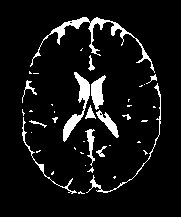

Magnetic Resonance Imaging (MRI) is a critical and widely used medical modality due to its noninvasive nature and ability to produce high-quality images of human organs and tissues. Segmentation in MRI refers to the process of dividing the acquired image data into specific tissues or regions of interest (ROIs). In the context of brain slice MRI data, this often involves distinguishing between cerebrospinal fluid (CSF), gray matter (GM), and white matter (WM), in 2D image slices as depicted in Fig. 1. Research topics on brain anatomy and functionality (e.g., Alzheimer’s disease, tumor detection, neurodegenerative processes, etc.) demand reliable segmentation tools since their outcomes directly impact the subsequent analysis of the brain slice MRI. Therefore, the development of any accurate MRI segmentation framework has to deal with the following issues:

| brain MRI slice | artifacts | ground truth | cartoon | texture |

(1) where can be interpreted as a smoother version of . With a little abuse of notation, we indicate the equation (1) as a cartoon-texture (CT) decomposition (even though we do not aim to compute a proper CT decomposition), where is the ‘cartoon’ depicting the structural component, and the ‘texture’ part including oscillatory components, like texture and noise, as shown in Figure 1.